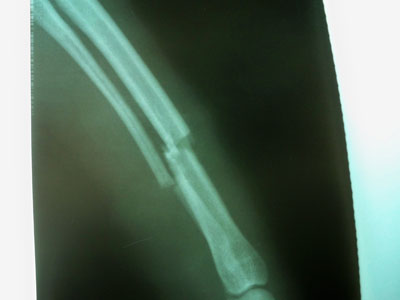

Ημίαιμο καφέ σκυλάκι μεσαίου μεγέθους 3-4 ετών με ιστορικό ατυχήματος στις 30/01/10.Προσκομίσθηκε στο ιατρείο και διαπιστώθηκε κάταγμα στο δεξί πρόσθιο άκρο.Το κάταγμα ήταν τέλειο και εγκάρσιο στο κάτω /3 της διάφυσης της δεξιάς κερκίδας και ωλένης.

Mετά την ανάταξη του κατάγματος τοποθετήθηκε μεταλλική πλάκα 2mm στην πρόσθια επιφάνεια της κερκίδας με 3 κοχλίες στο κεντρικό και 3 κοχλίες στο περιφερικό τμήμα.Συρραφή του μυ΄ι΄κού τοιχώματος έγινε με interlocking ραφή και του δέρματος με π ραφές.